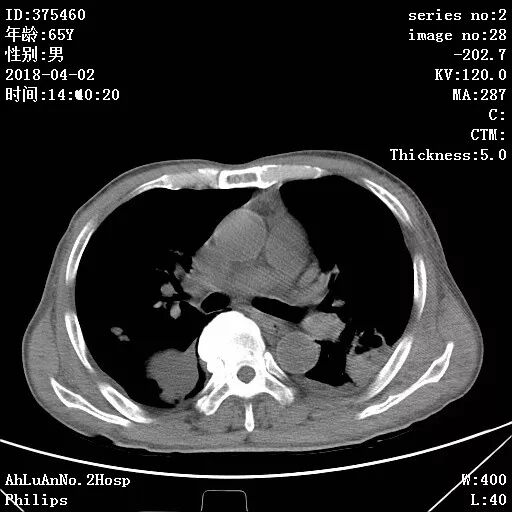

患者男,65岁,因“咳嗽、咳痰1月余,发热1周”入院。

两肺可见多发斑片状及气囊样阴影,部分气囊样影内可见气液平面,两侧胸膜腔可见少量液性密度影聚集。

结果:金黄色葡萄球菌肺炎

显示,白细胞计数和中性粒细胞百分比升高,可有核左移及中毒颗粒。本病的胸部X线特征常表现为肺段或肺叶实变,或呈小叶样浸润,其中有单个或多发的液气囊腔。

X线阴影的易变性是本病的另一重要特征,其常表现为一处炎性浸润消失而在另一处出现新的病灶,或很小的单一病灶发展为大片阴影。